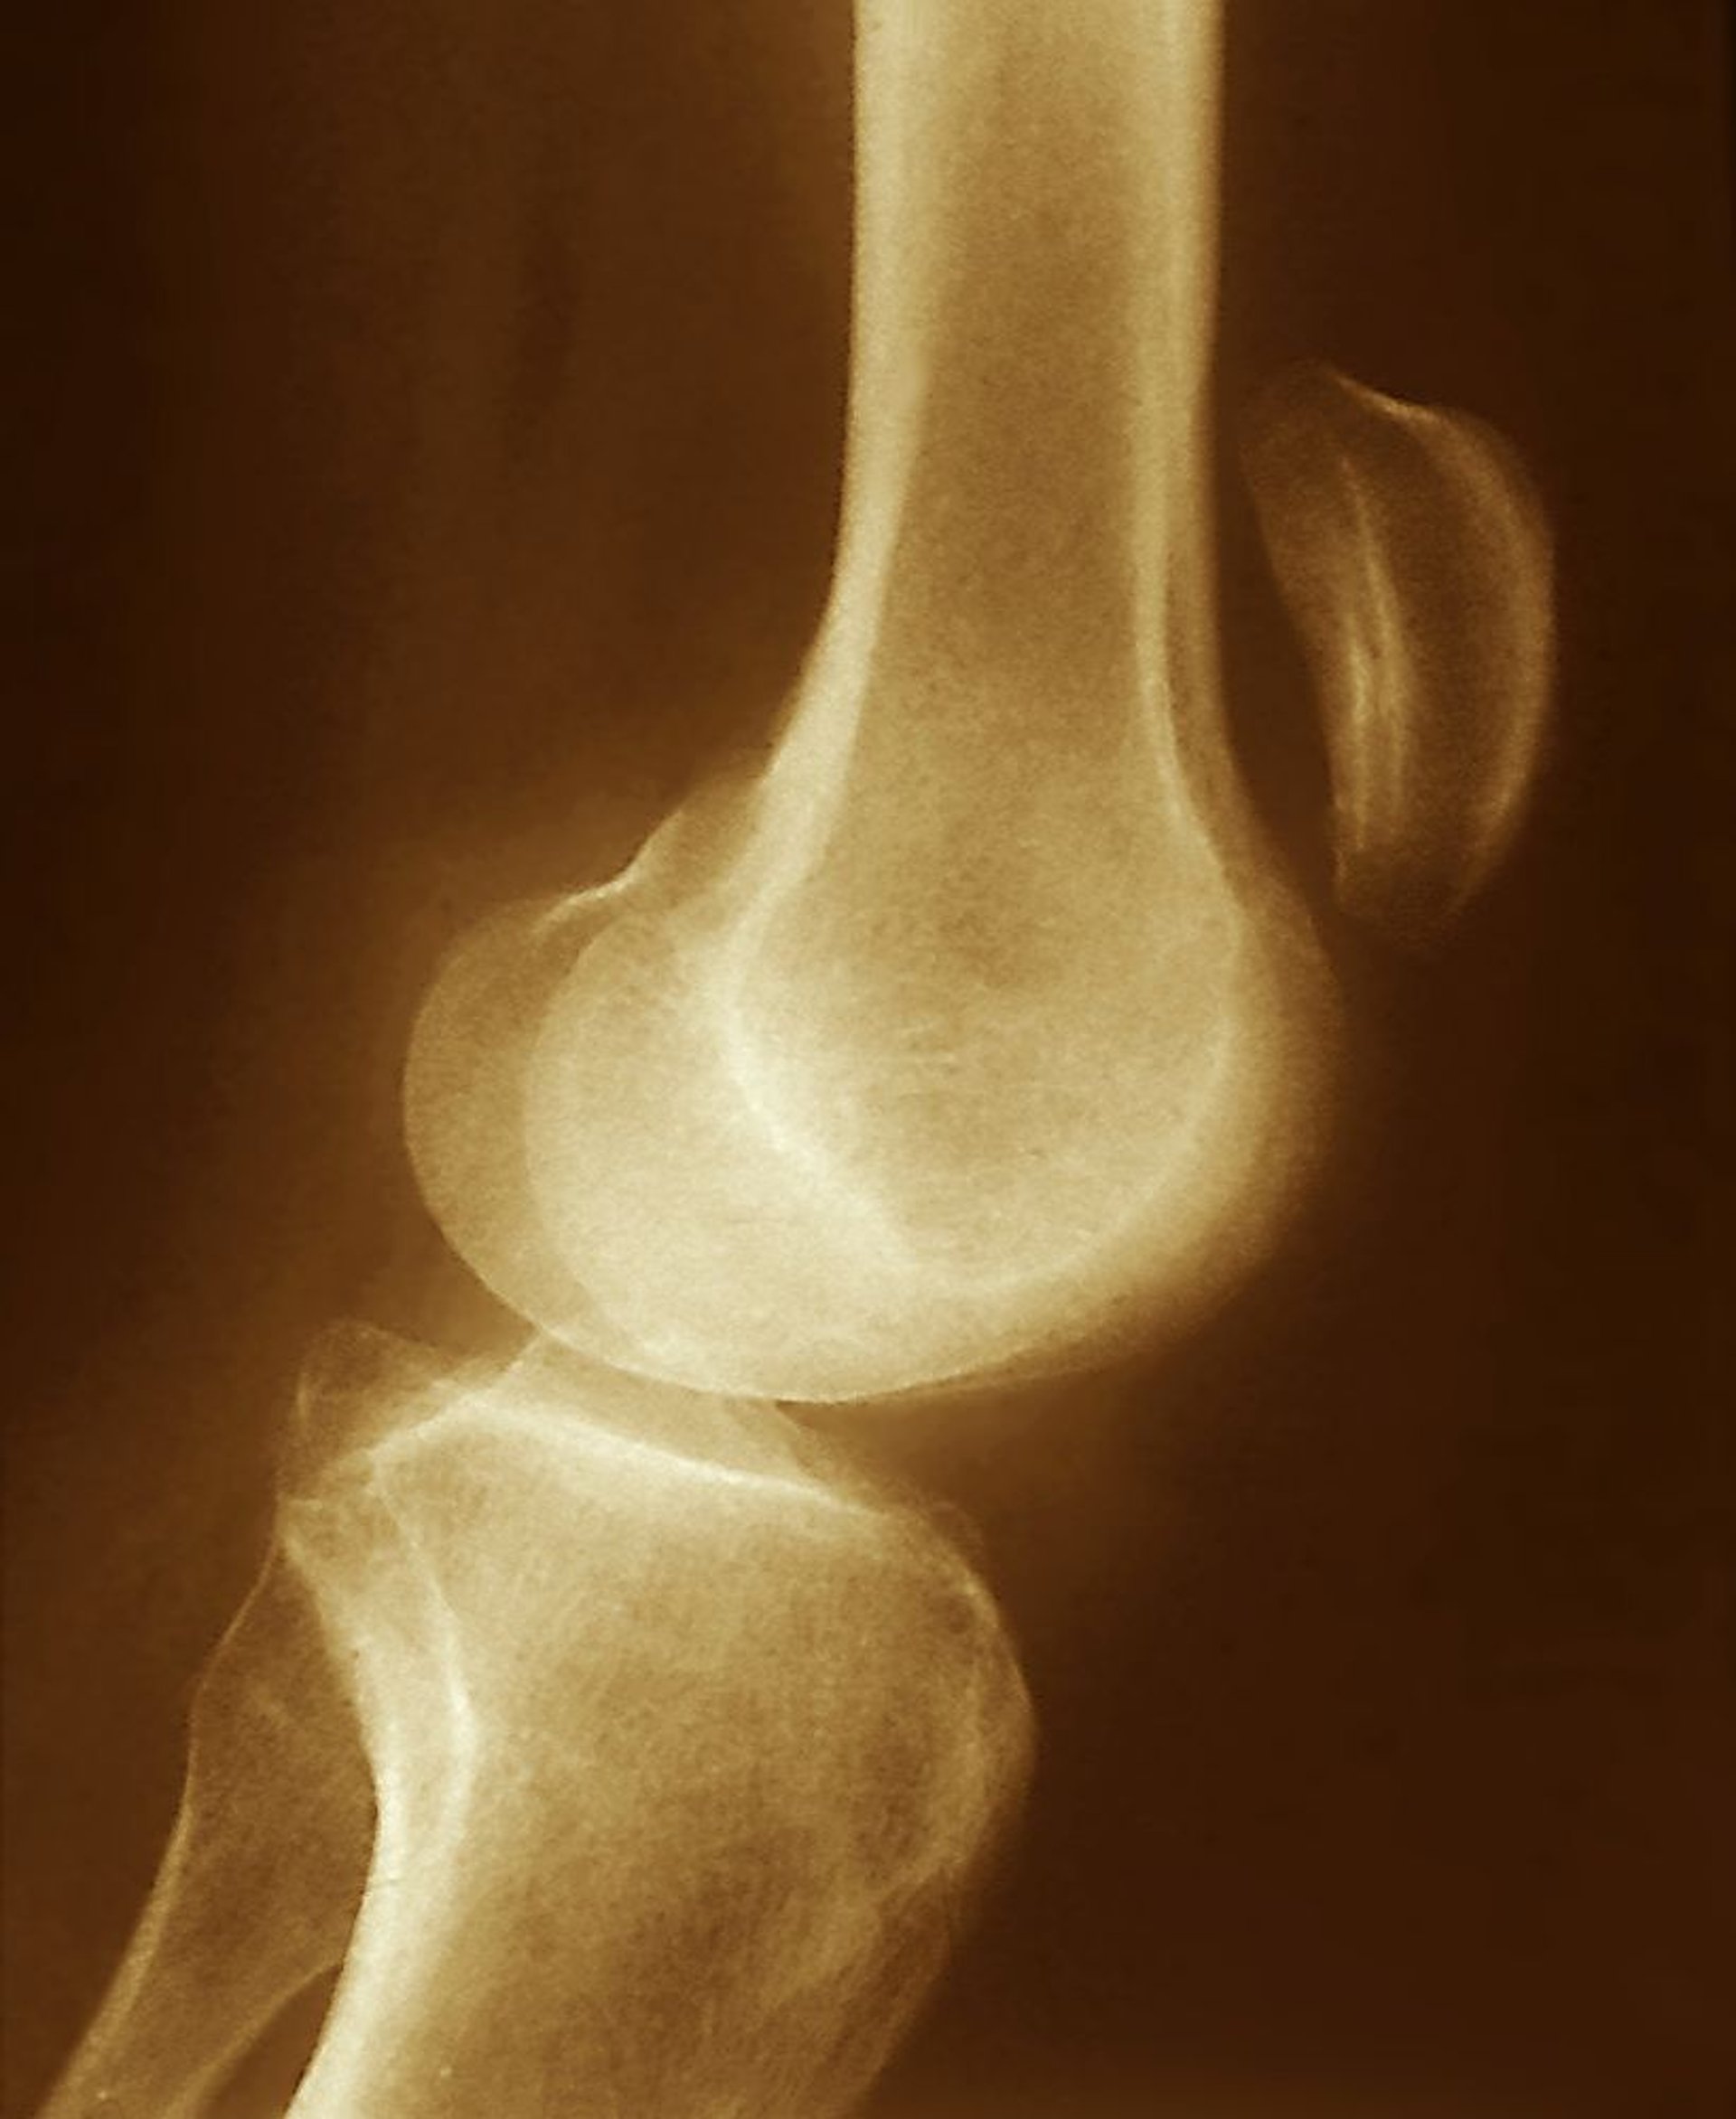

Desgarro del tendón rotuliano

El desplazamiento superior de la rótula visto en esta radiografía (muy por encima de la articulación de la rodilla) sugiere un desgarro del tendón rotuliano, con contracción del músculo cuádriceps sin oposición.

ZEPHYR/SCIENCE PHOTO LIBRARY